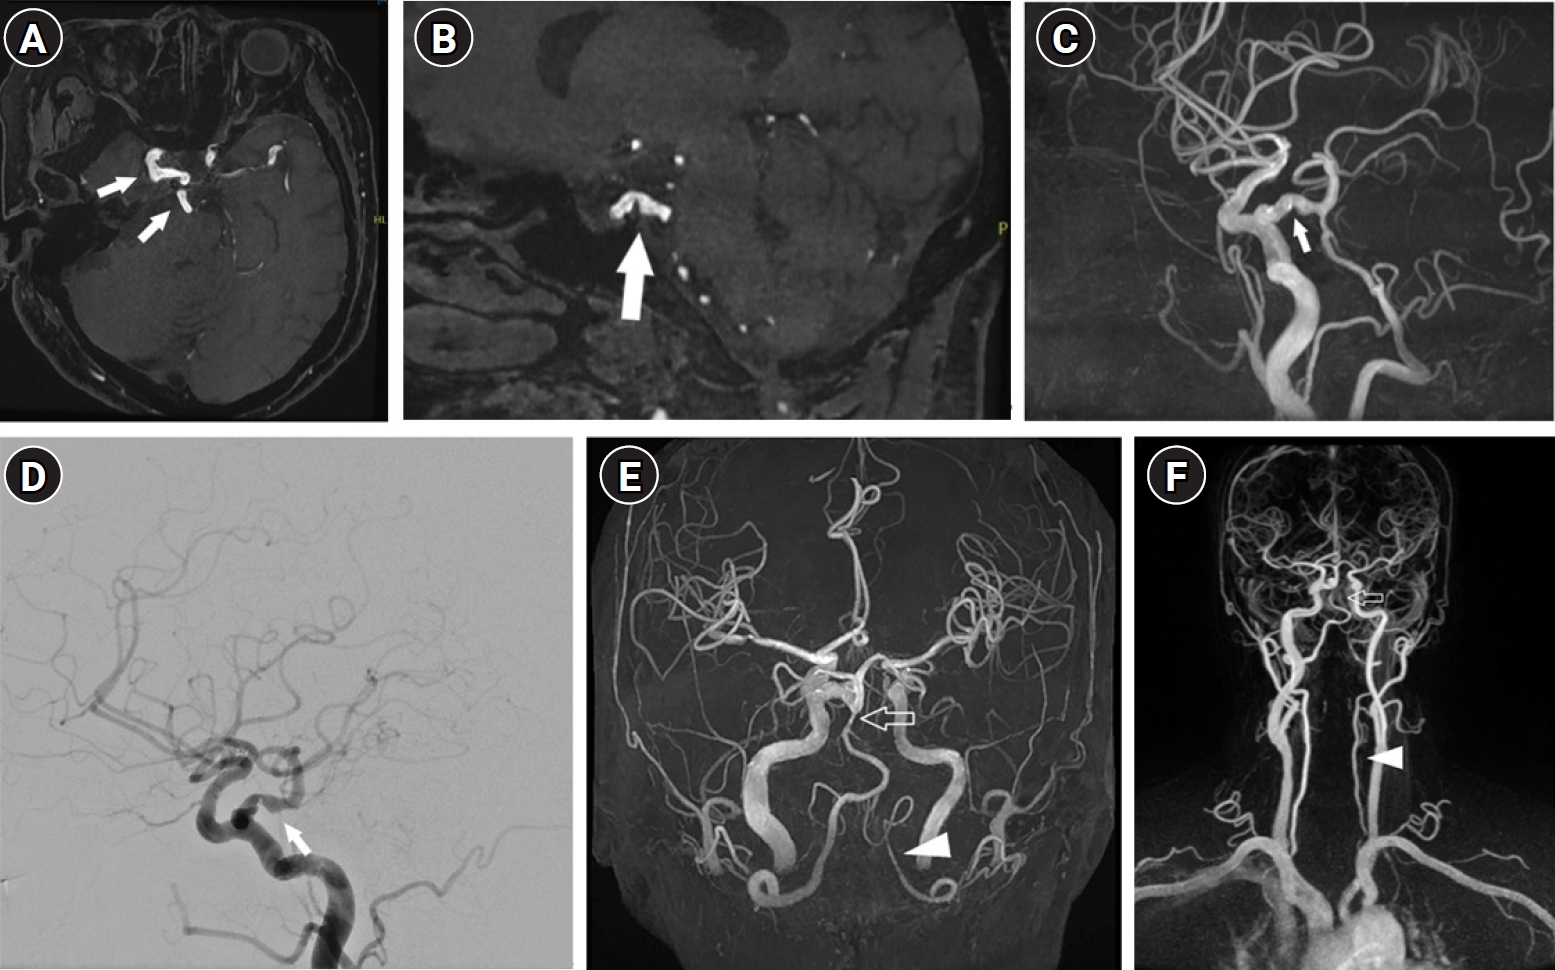

Atherosclerotic changes in an intrasellar persistent trigeminal artery in a patient presenting with dizziness: a case report from Korea

Jieun Byun

, Boeun Lee

Ewha Med J 2026;49(2):e12.